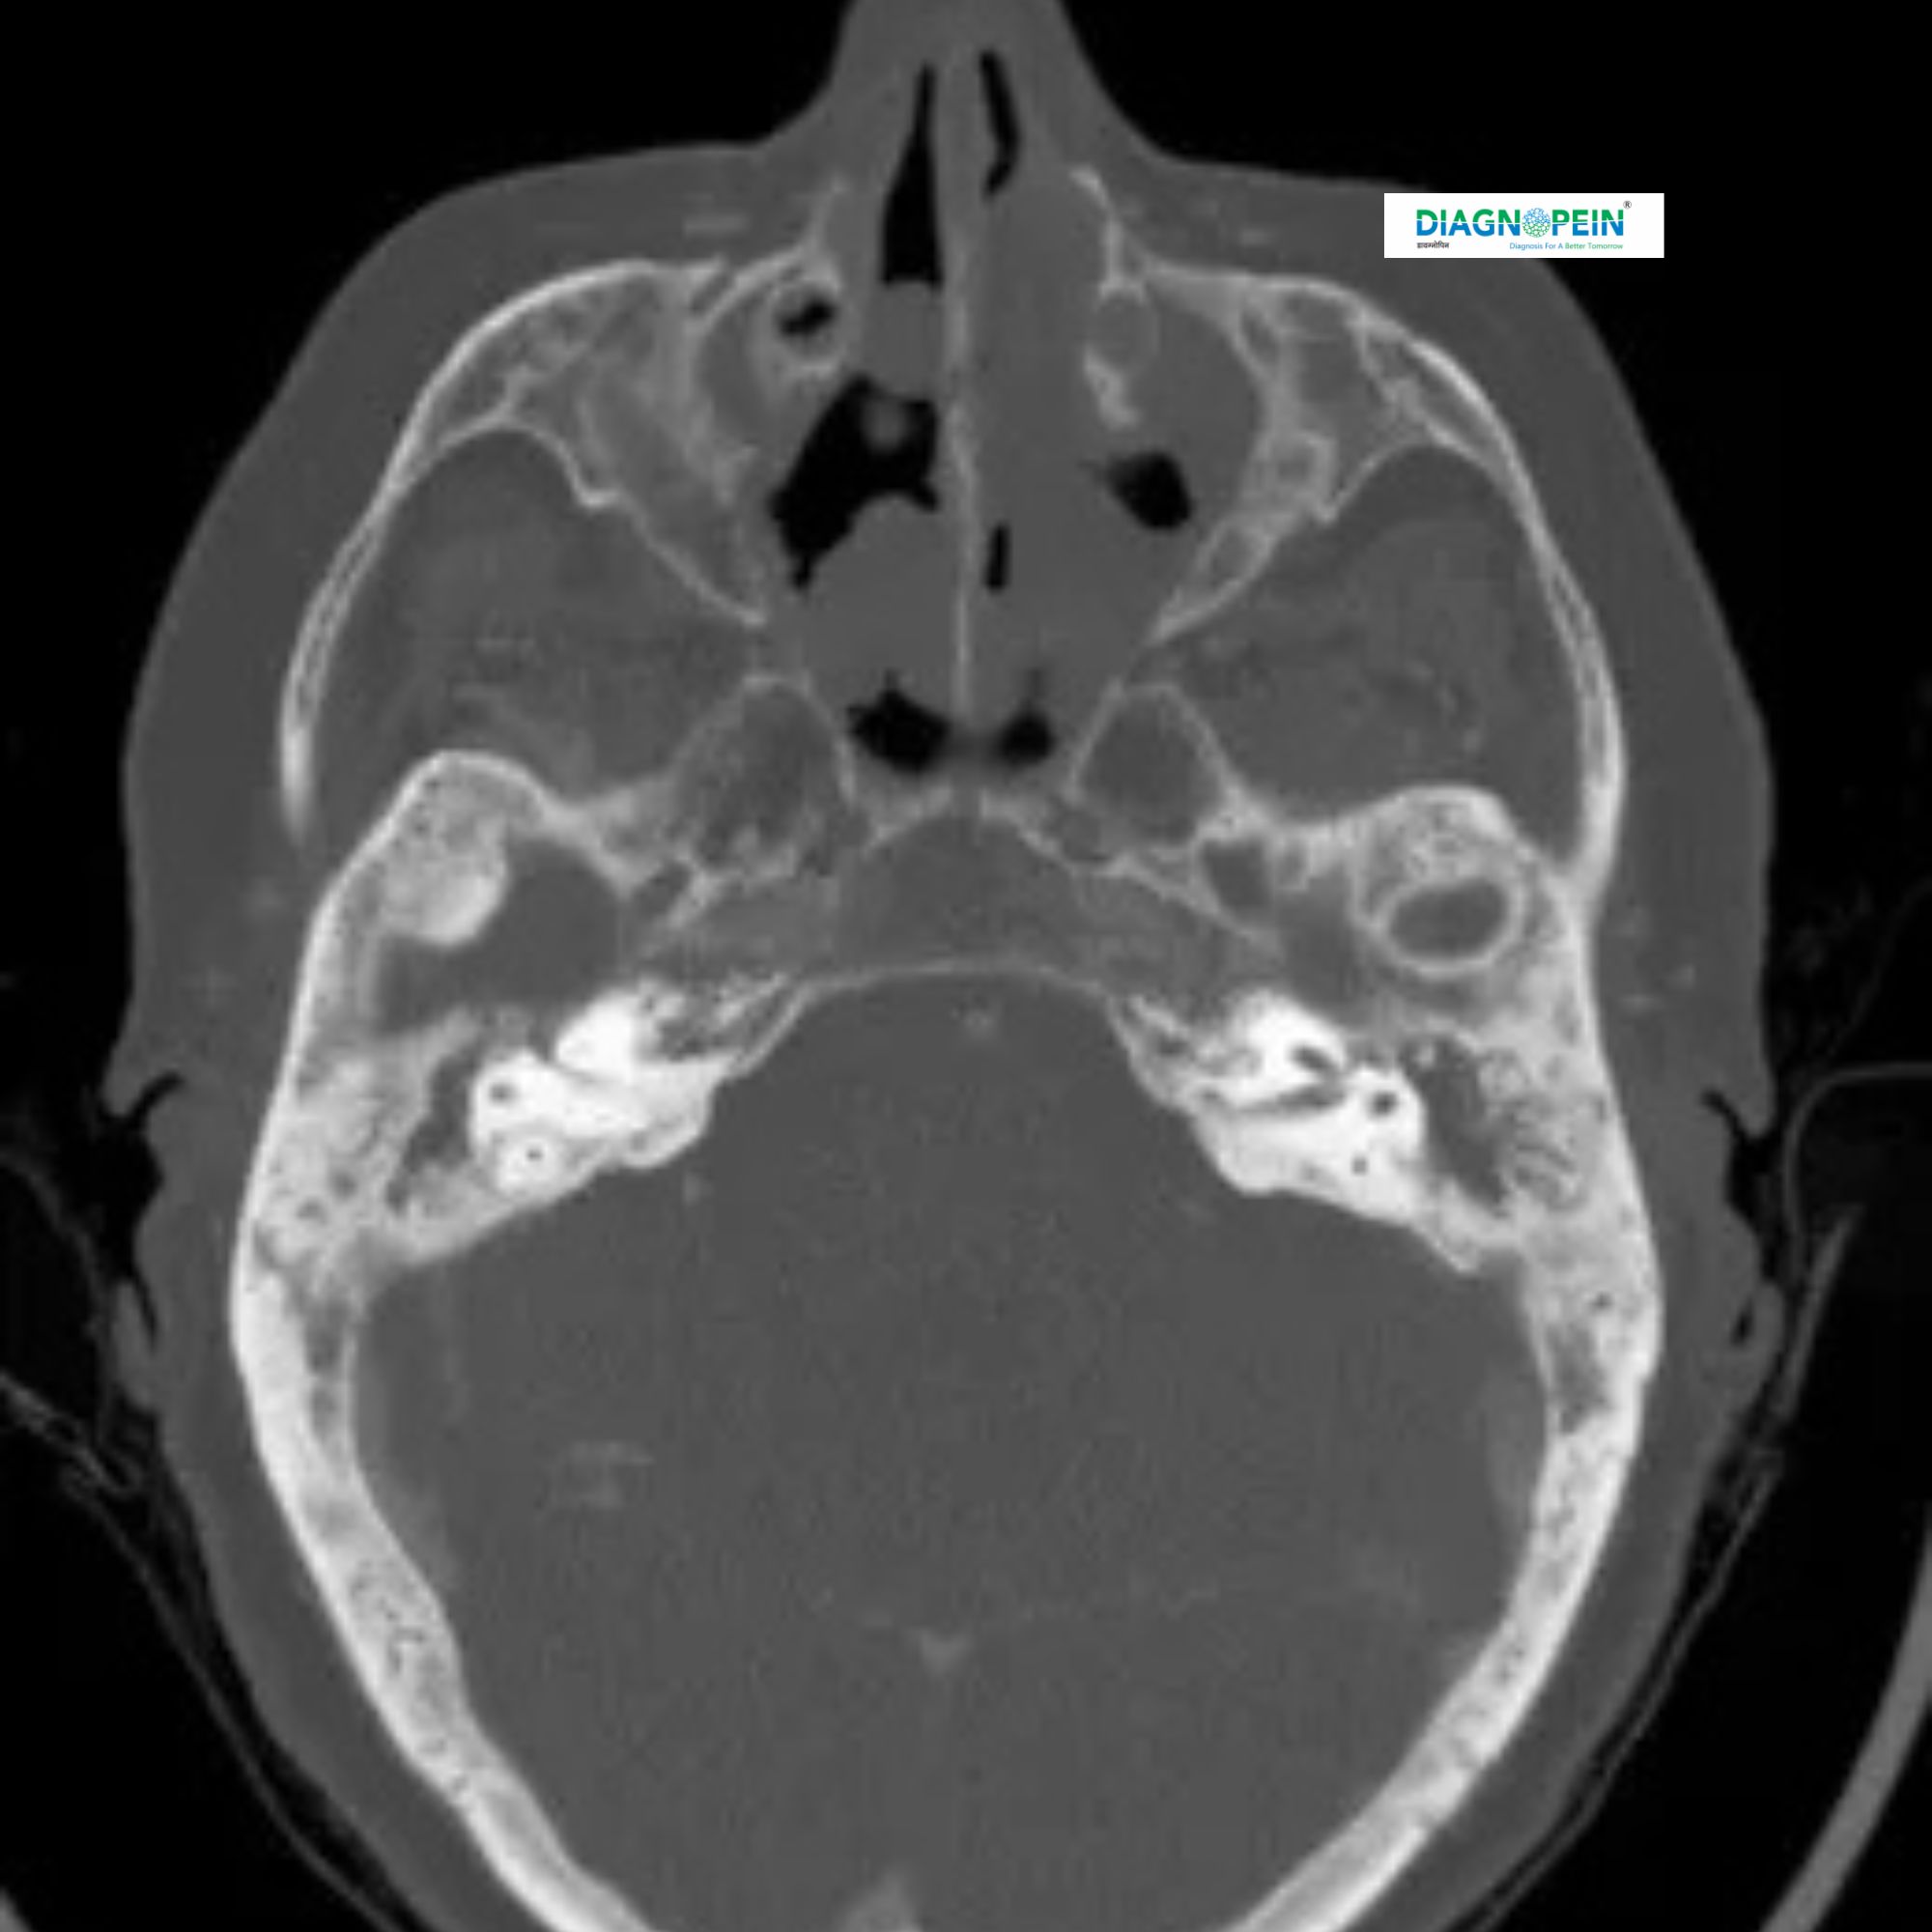

A CT Scan of the Paranasal Sinuses with Contrast is a highly detailed imaging test that helps doctors examine the sinus cavities, nasal passages, and surrounding bones. Using a special contrast dye, this scan provides enhanced images to detect sinus infections, polyps, cysts, tumors, or other abnormalities that may not be visible on a regular CT scan or X-ray.

A CT (Computed Tomography) scan uses advanced X-ray technology and computer processing to create cross-sectional images of your sinuses. When contrast material (a safe dye) is injected into your bloodstream, it highlights blood vessels and soft tissues, helping your doctor identify inflammation, infections, or structural problems with greater clarity.

This scan covers all paranasal sinuses, including:

1. Maxillary sinuses (under the eyes)

2. Ethmoid sinuses (between the eyes)

3. Frontal sinuses (in the forehead)

4. Sphenoid sinuses (behind the eyes)